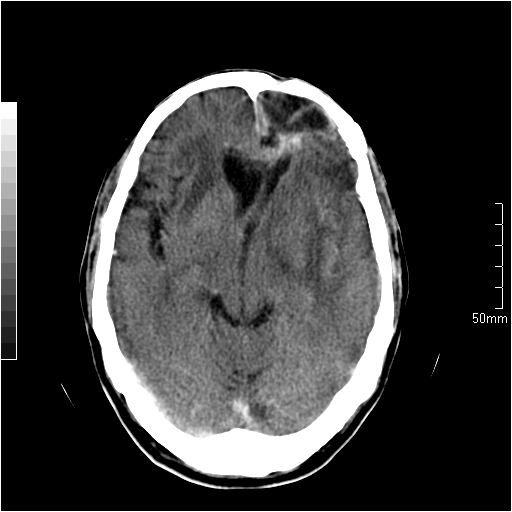

以下是引用天南地北在2007-6-25 12:39:00的发言:[br]有占位效应[br]支持术后复发

以下是引用zjzjr在2007-6-25 12:38:00的发言:[br]左侧复发,右侧转移。